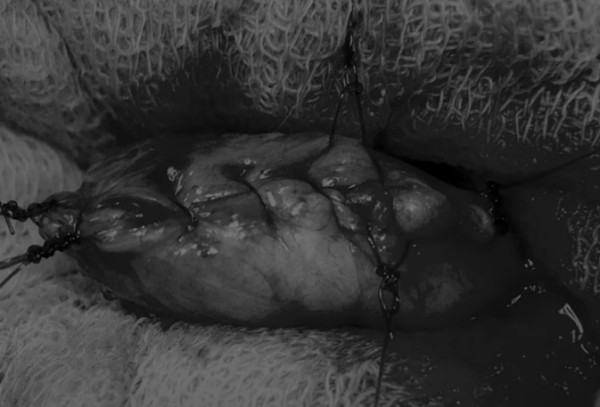

图4 这张图显示了从膀胱中取出的大量结石

完成膀胱内冲洗后,应通过导尿管反向冲洗膀胱;砂样结石和血块会被冲到切口表面(图5)

戳下方点亮图片

文章详情图片

图5 通过导尿管注入无菌生理盐水反向冲洗,可以去除微小的结石(箭头)和夹杂在膀胱黏膜皱褶中的砂样结石,以及可能在手术中形成的血块